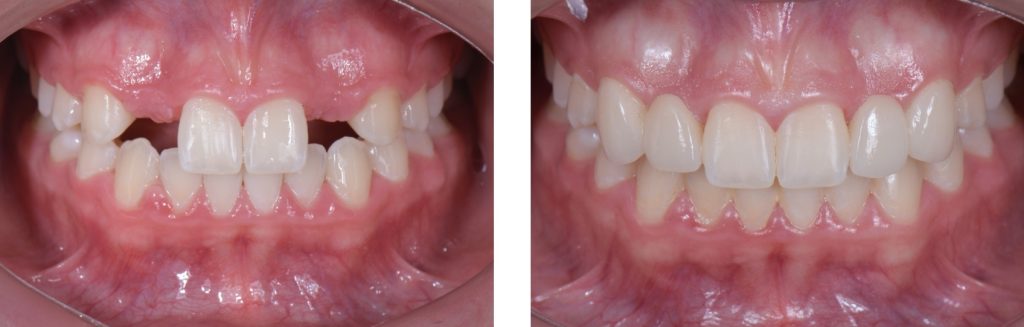

In this case, a 16-year-old female (Figs. 13-23) presented with congenitally missing lateral incisors with significantly undersized canines that were out of occlusion. Both these specific features meant that from a functional and esthetic standpoint (tooth position and size), the canines required additional contour to attain a favorable occlusal contact and a more dominant contour, characteristic of a maxillary canine.

So, I needed to make sure that there was enough space for the restorative material. A purely additive wax-up was required to attain a mockup, verifying that the proposed contours were esthetically pleasing. This can be obtained either by an analogic approach (Fig. 15) or a digital approach (Fig. 16).

Incisally, there was no reduction required, the reduction was minimal, and from a cervical perspective, a 0.5 mm finish line was prepared (Fig. 17). This allowed our team to do a fundamentally additive design.

The undersized canines were out of function, removing all protective coverage for the lateral incisors. This provided a unique opportunity and indication for the most conservative scenario of a cantilevered RBFDP.

When considering a zirconia crown, we needed to ensure there was sufficient room for the wall thickness to be a minimum of 0.3 mm (ideally between 1.0 mm and 1.5 mm), an incisal reduction of 2.0 mm, and a visible and continuous circumferential chamfer with a reduction of at least 0.5 mm at the gingival margin. The patient’s preliminary condition allowed us to accomplish these space requirements with hardly any tooth reduction (Fig. 17).